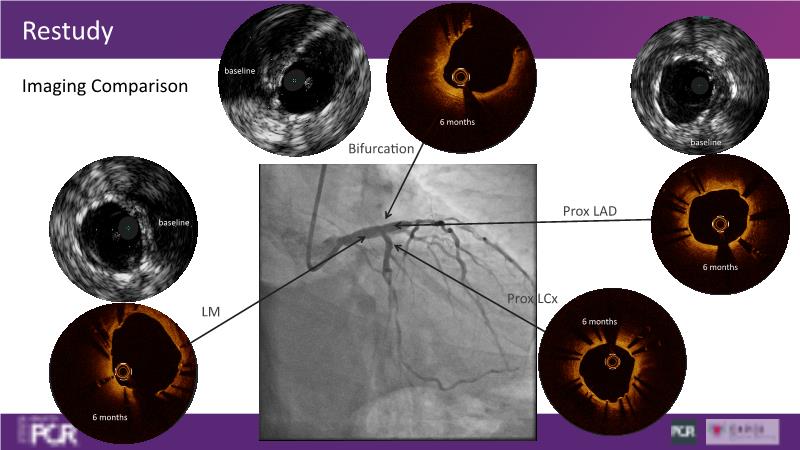

Join this session to delve into the unmet needs concerning drug-eluting stents (DES), including poor long-term clinical outcomes, with up to a 50% MACE rate at 10 years, and a non-plateauing 2-3% annual event rate. Explore how DynamX Bioadaptor technology addresses these challenges by maintaining the established flow lumen and restoring hemodynamic modulation of the artery. Discover the sustained clinical benefits demonstrated in a 2-year RCT, potentially establishing a new treatment standard for CAD patients. Gain insights into patient types benefiting most in clinical practice, such as those at higher risk of restenosis (e.g., LAD disease, long lesions, small vessels, co-morbidities), and younger patients with longer lifespans.